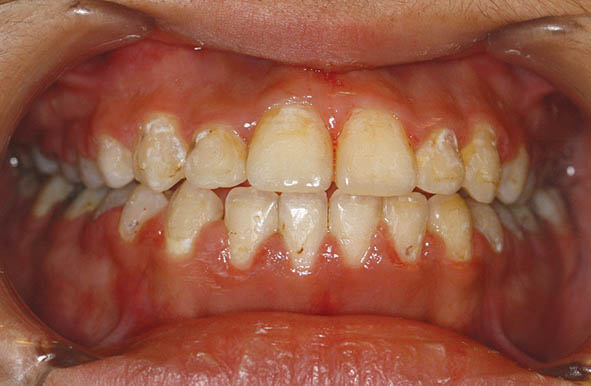

در بیمار اپن بایت (شکل 38-3 الی 40-3) در هر دو سمت چپ و راست یک مینی اسکرو در سمت باکال (شکل 41-3 الی 43-3) و یکی در سمت پالاتال (شکل 47-3) قرار میدهیم. آرچ وایری که میگذاریم را در ناحیه بین کانین و پرمولر اول قطع میکنیم تا دندانهای خلفی با قدامی روی یکدیگر اثری نداشته باشند. وقتی آرچوایر سه تکه باشد دندانهای سگمنت قدام و خلف جداگانه مرتب میشوند. چهار قطعه چین الاستیک از مینی اسکرو باکال به براکت دندانهای پرمولرها و مولرها میاندازیم. چون گردن مینی اسکروها برای چهار قطعه چین الاستیک کوچک است، لذا یک سیم لیگاچور از درون این چهار قطعه چین الاستیک رد میکنیم و آن سیم لیگاچور را به مینی اسکرو درگیر میکنیم تا یک نیروی اینترود کننده روی سمت باکال سگمنت خلفی اعمال شود. از سمت پالاتال هم چند باتن میچسبانیم و همین کار را در سمت پالاتال انجام میدهیم. البته در شکل 41-3 الی 43-3 دندانها در سمت باکال زیادتر از سمت پالاتال اینترود شدند، لذا سمت باکال با سیم لیگاچور به مینی اسکرو وصل شده تا در همان وضعیت بماند.

شکل 38-3

شکل 39-3

شکل 40-3

شکل 38-3 الی 40-3: اپن بایت شدید